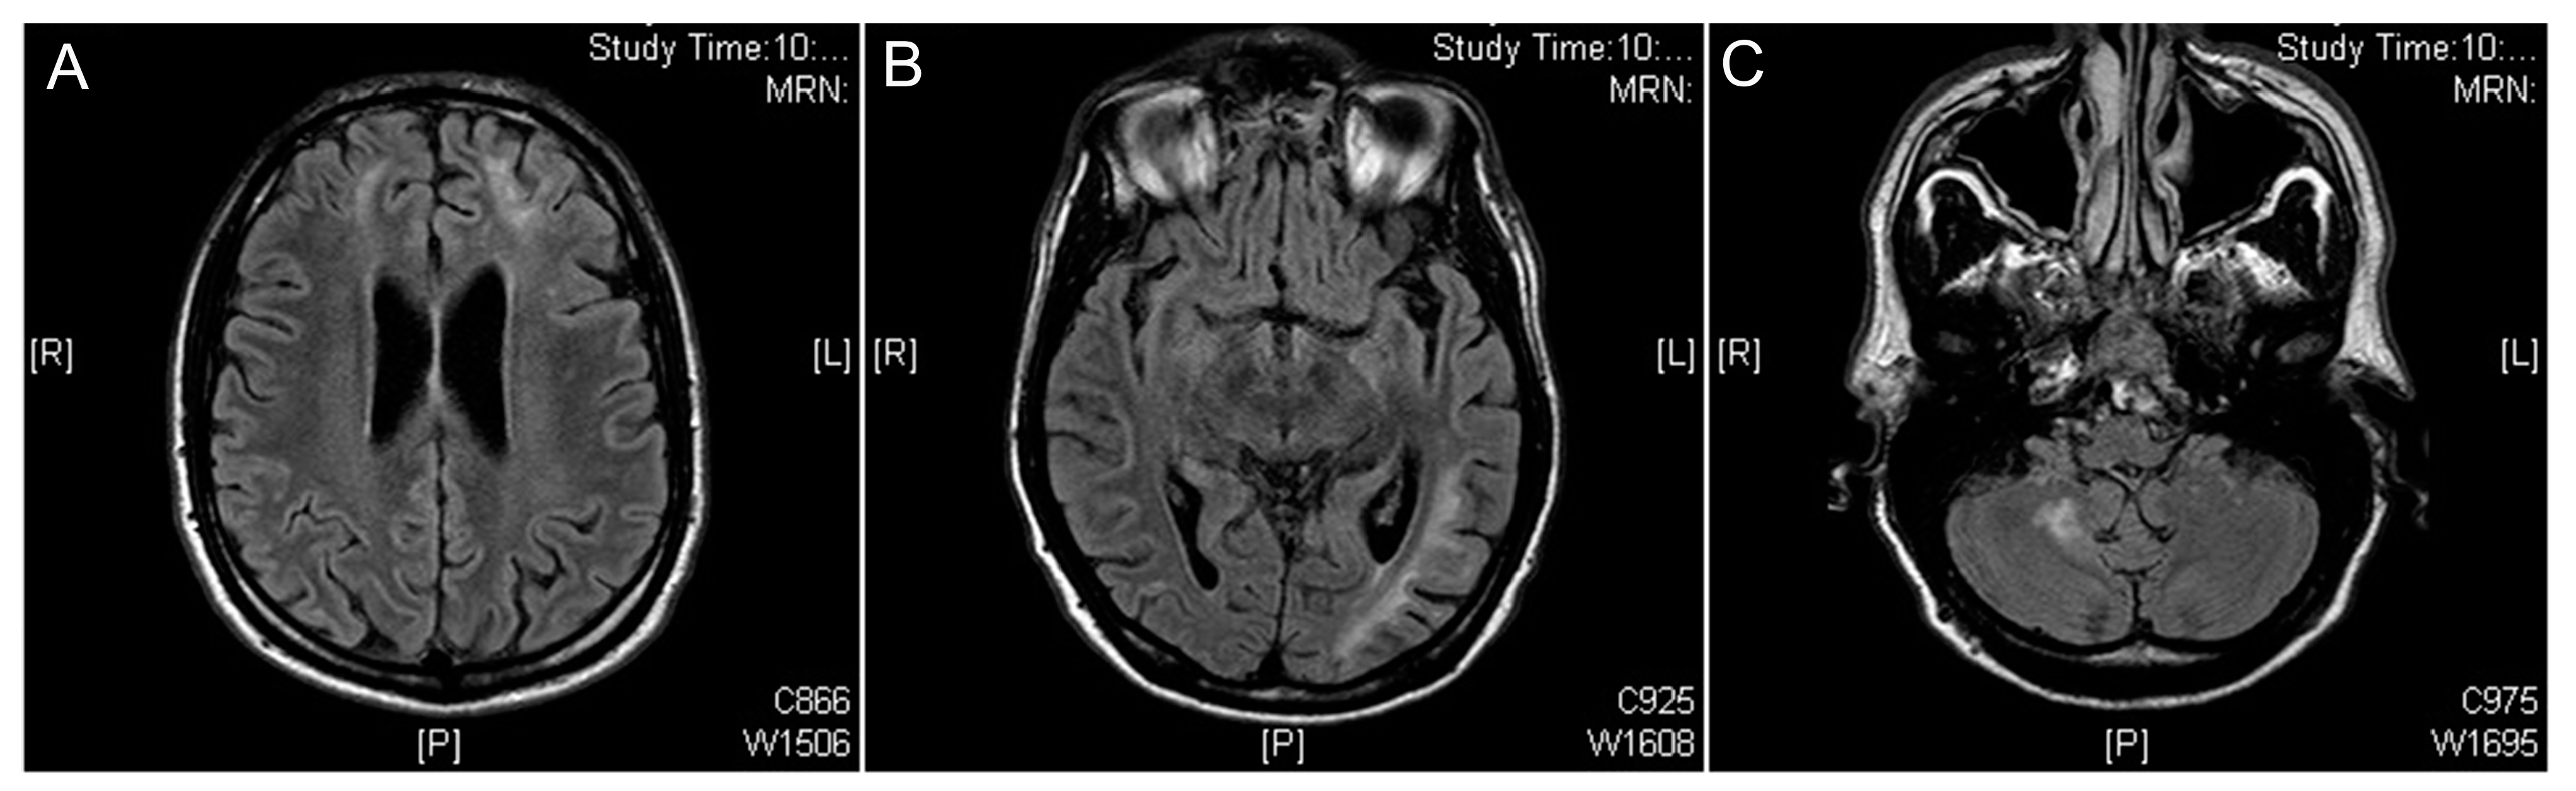

2.3. Toxoplasmosis

- Pereira-Chioccola, V.L.; Vidal, J.E.; Su, C. Toxoplasma gondiiinfection and cerebral toxoplasmosis in HIV-infected patients. Future Microbiol. 2009, 4, 1363–1379. [Google Scholar] [CrossRef]